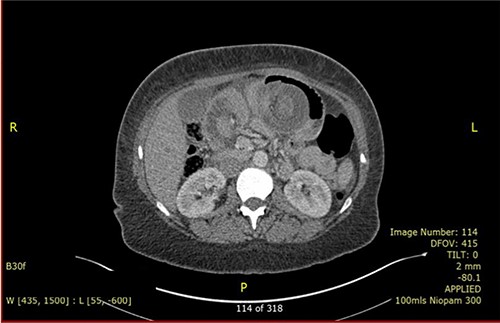

Nevertheless, the patient re-presented 4 months later with similar symptoms. She reported having no issue with bowel after the previous operation. On presentation, her blood results were unremarkable with normal inflammatory markers and lactate. Repeated CT (Fig. 3) again revealed intussusception of small bowel with signs of bowel ischaemia. She was taken to theatre for emergency laparotomy. Intraoperatively, there were dense adhesions with four quadrant purulent peritonitis and a small perforation was found on the anterior staple line of ileo-ileal anastomosis. Distal limb of small bowel had intussuscepted retrograde into the anastomosis, causing obstruction of both thickened proximal limbs. Attempt at the reduction of intussusception was unsuccessful, hence decision was made to proceed with resection and Roux-en-Y reconstruction. Ileo-ileal anastomosis was recreated with stapled side-to-side anastomosis, and roux loop was re-anastomosed just distal to it with double-layered, sutured end-to-side jejunal-ileal anastomosis. Patient made an uneventful recovery and was discharged after a week. Histology of resected small bowel segment in both operations did not show evidence of localized inflammation or neoplasia and the cause of intussusception is not apparent.

CT scan is the preferred imaging modality for early identification of intussusception [9]. Characteristic findings are target signs and multiple concentric rings as seen in this case. While CT can diagnose intussusception, there is limitation in identifying its underlying aetiology. Other imaging modalities, such as plain abdominal films or ultrasonography, can be used but is less practical in diagnostic purpose compared to CT scan.